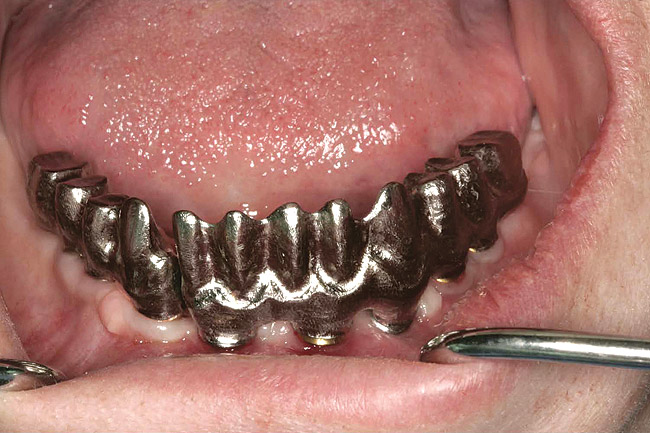

The goal is to avoid systemic drugs if possible, so as to not build bacterial resistance. As mentioned before, compliance can be a problem with prescription medications. When locally administered antibiotics such as minocycline hydrochloride are used, there are no compliance concerns. The patient is treated chairside, and the antibiotic is syringed into each pocket, where it stays and continues to provide antibiotic action for up to 30 days.14 Figure 2 depicts the administration of a locally applied antibiotic. Locally administered antibiotics have an advantage in that they are targeted right at the source of infection: the antibiotic is absorbed right through the epithelium on contact, so there are effective therapeutic levels exactly where they are most needed.15,16 Systemic antibiotics pass through the digestive system, where much of the active medication is absorbed and metabolized before it even reaches the target area. Unlike systemic antibiotics, where blood concentrations of the drug continue to lessen as they are metabolized in a short amount of time, locally administered antibiotics such as minocycline hydrochloride can provide a sustained release of a constant, effective level or concentration of the drug for 2 weeks or longer.14